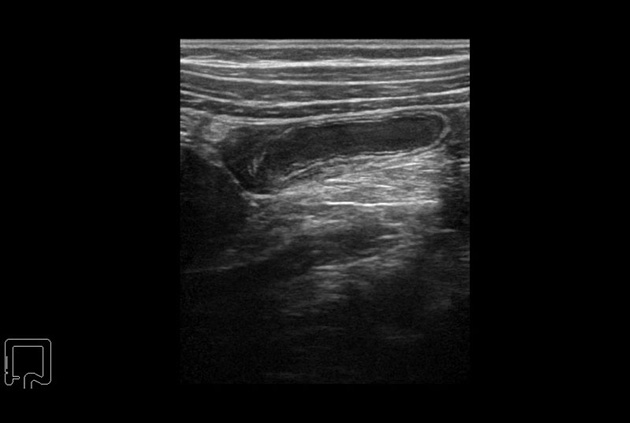

Our smallest footprint allows for enhanced contact in tight spaces

Our newest probe, the L51K allows the surgeon access to difficult-to-reach areas that no other probe on the market can go. The unique design and proximal location of the attaching mechanism provides full wrist articulation and easier grasp and release.